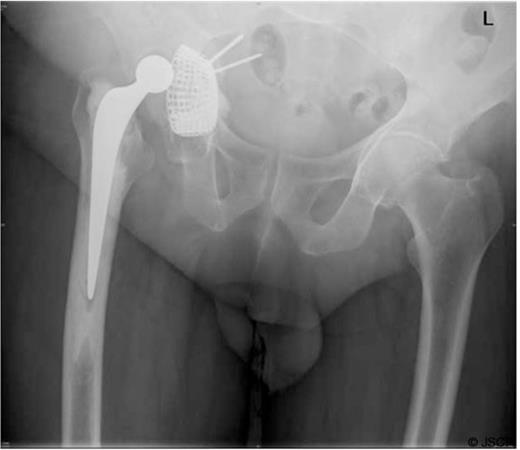

A post-operative radiograph (Figure 1) revealed medial migration of the acetabular construct prompting CT scans of his pelvis.

A pelvic radiograph showing migration of the acetabular construct